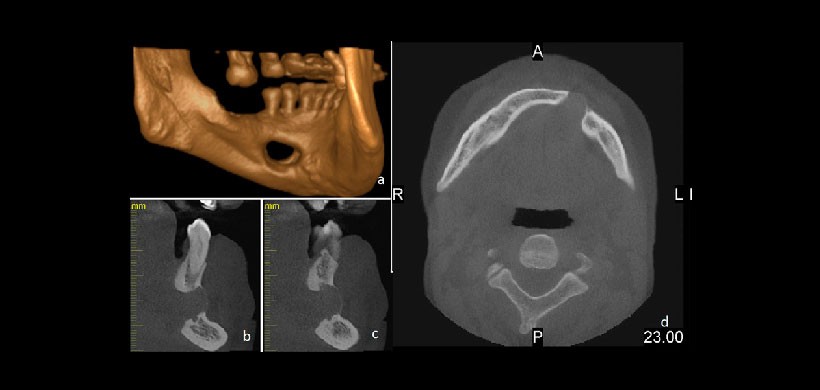

Fig 2. Las imágenes tomadas a partir del examen tomografía volumétrica (CBCT). (A) Representación tridimensional. El defecto parece haber erosionado la corteza bucal. (B, C) Las imágenes en sección transversal de la zona del defecto que muestra la relación del nervio alveolar inferior y los ápices de los dientes con el defecto. (D) Vista axial que muestra la expansión bucal causada por el defecto. A, anterior; L, izquierda; P, posterior; R, derecha.